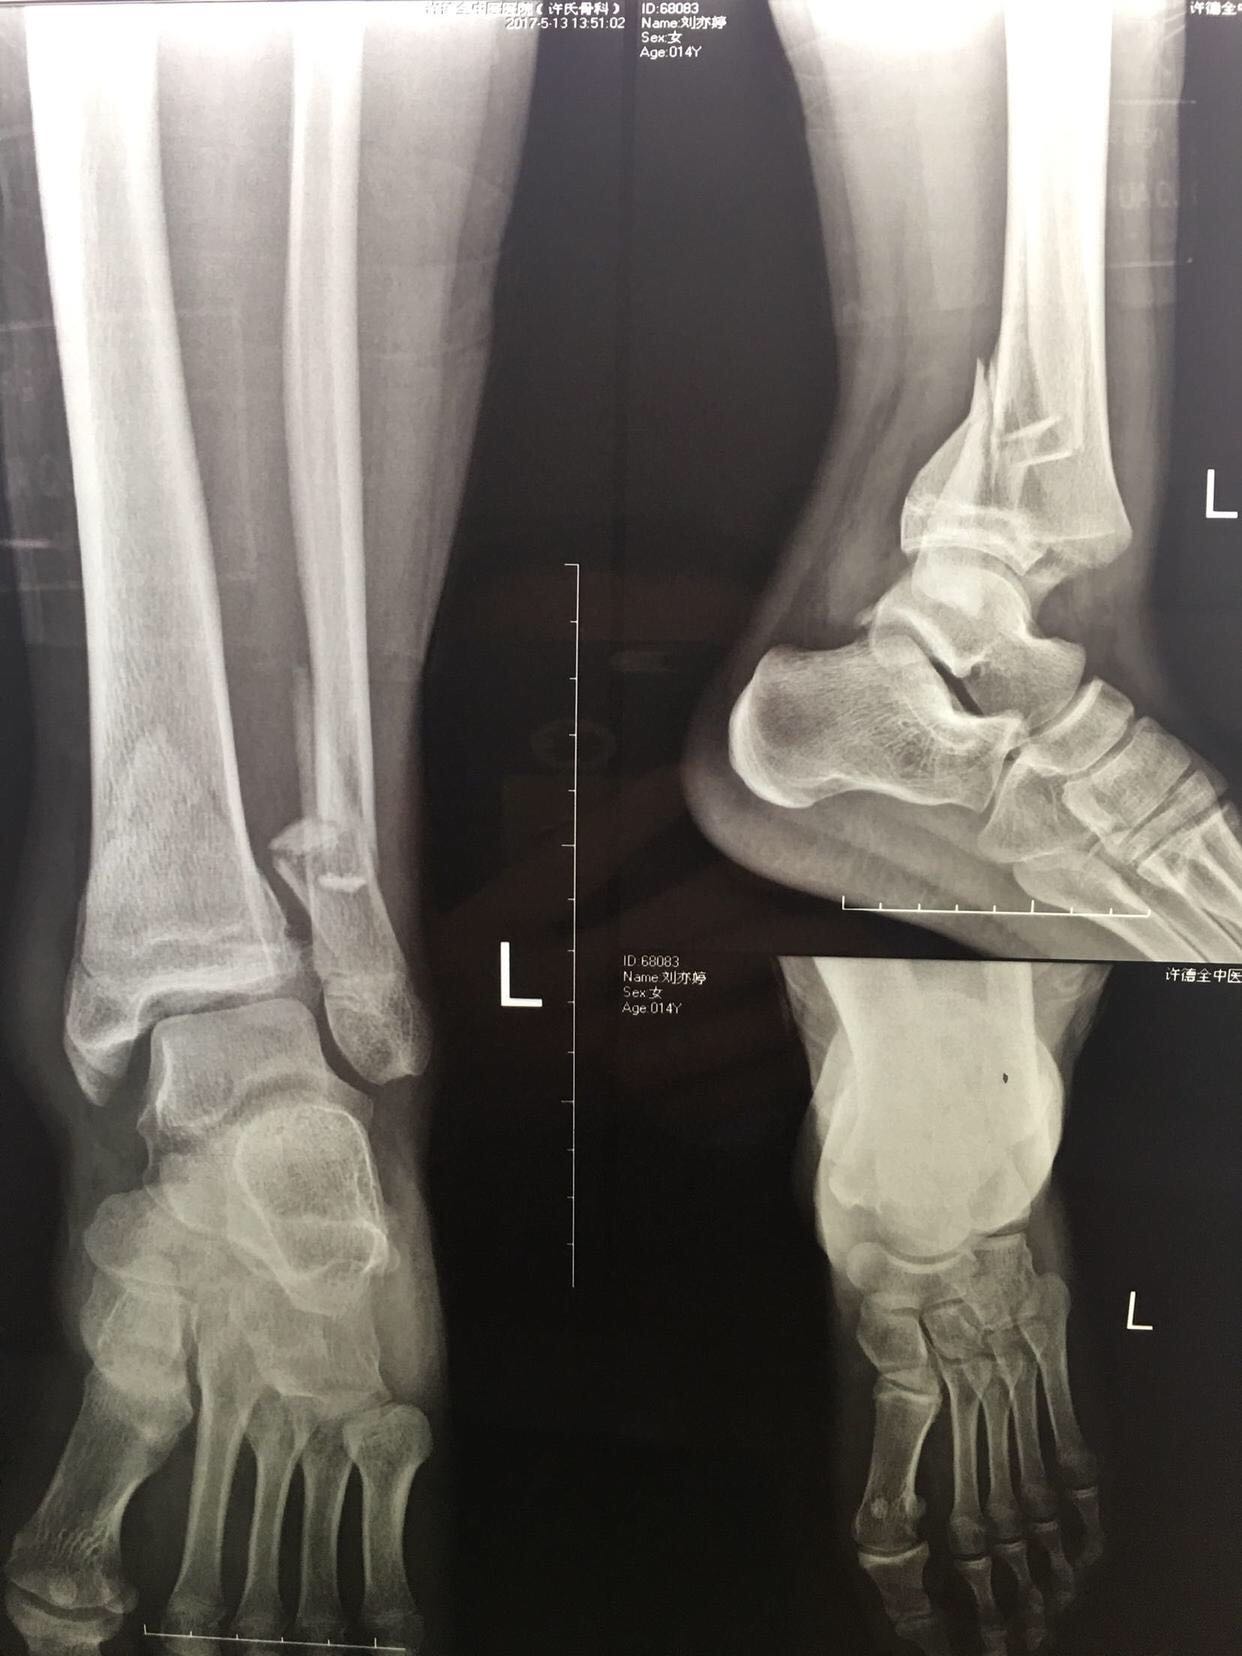

患儿,女,13岁,摔伤后左踝肿痛,活动受限4小时。

左踝部肿胀,畸形,局部皮色皮温正常,压痛,纵叩痛阳性,活动受限,末梢感觉血运正常。

急诊在局麻行左跟骨结节骨牵引术一周。今日在腰麻下行切复内固定术,术后抗炎,消肿止痛等处理,石膏托制动3-4周。